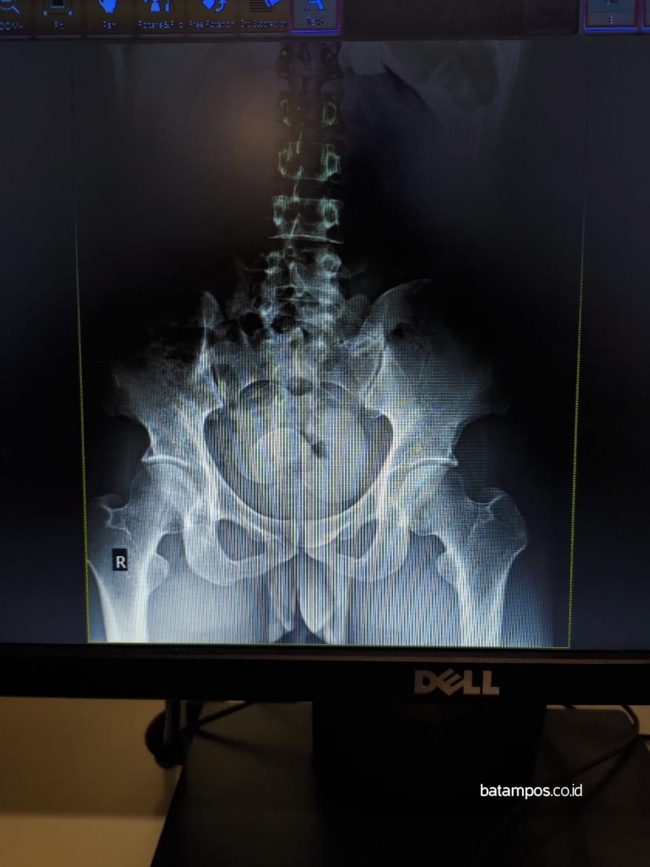

Hasil rontgen ditubuh FES yang di dalamnya terdapat tiga kapsul berisi 303 gram narkotika jenis sabu. Foto: Bea Cukai Batam untuk batampos.co.id

“Di Awal Bros tubuh pelaku di rontgen dan ditemukan di dalamnya ada tiga benda asing menyerupai kapsul yang ternyata sabu (methamphetamine),” jelasnya.

Berat barang haram tersebut lanjutnya sekitar 303 gram.